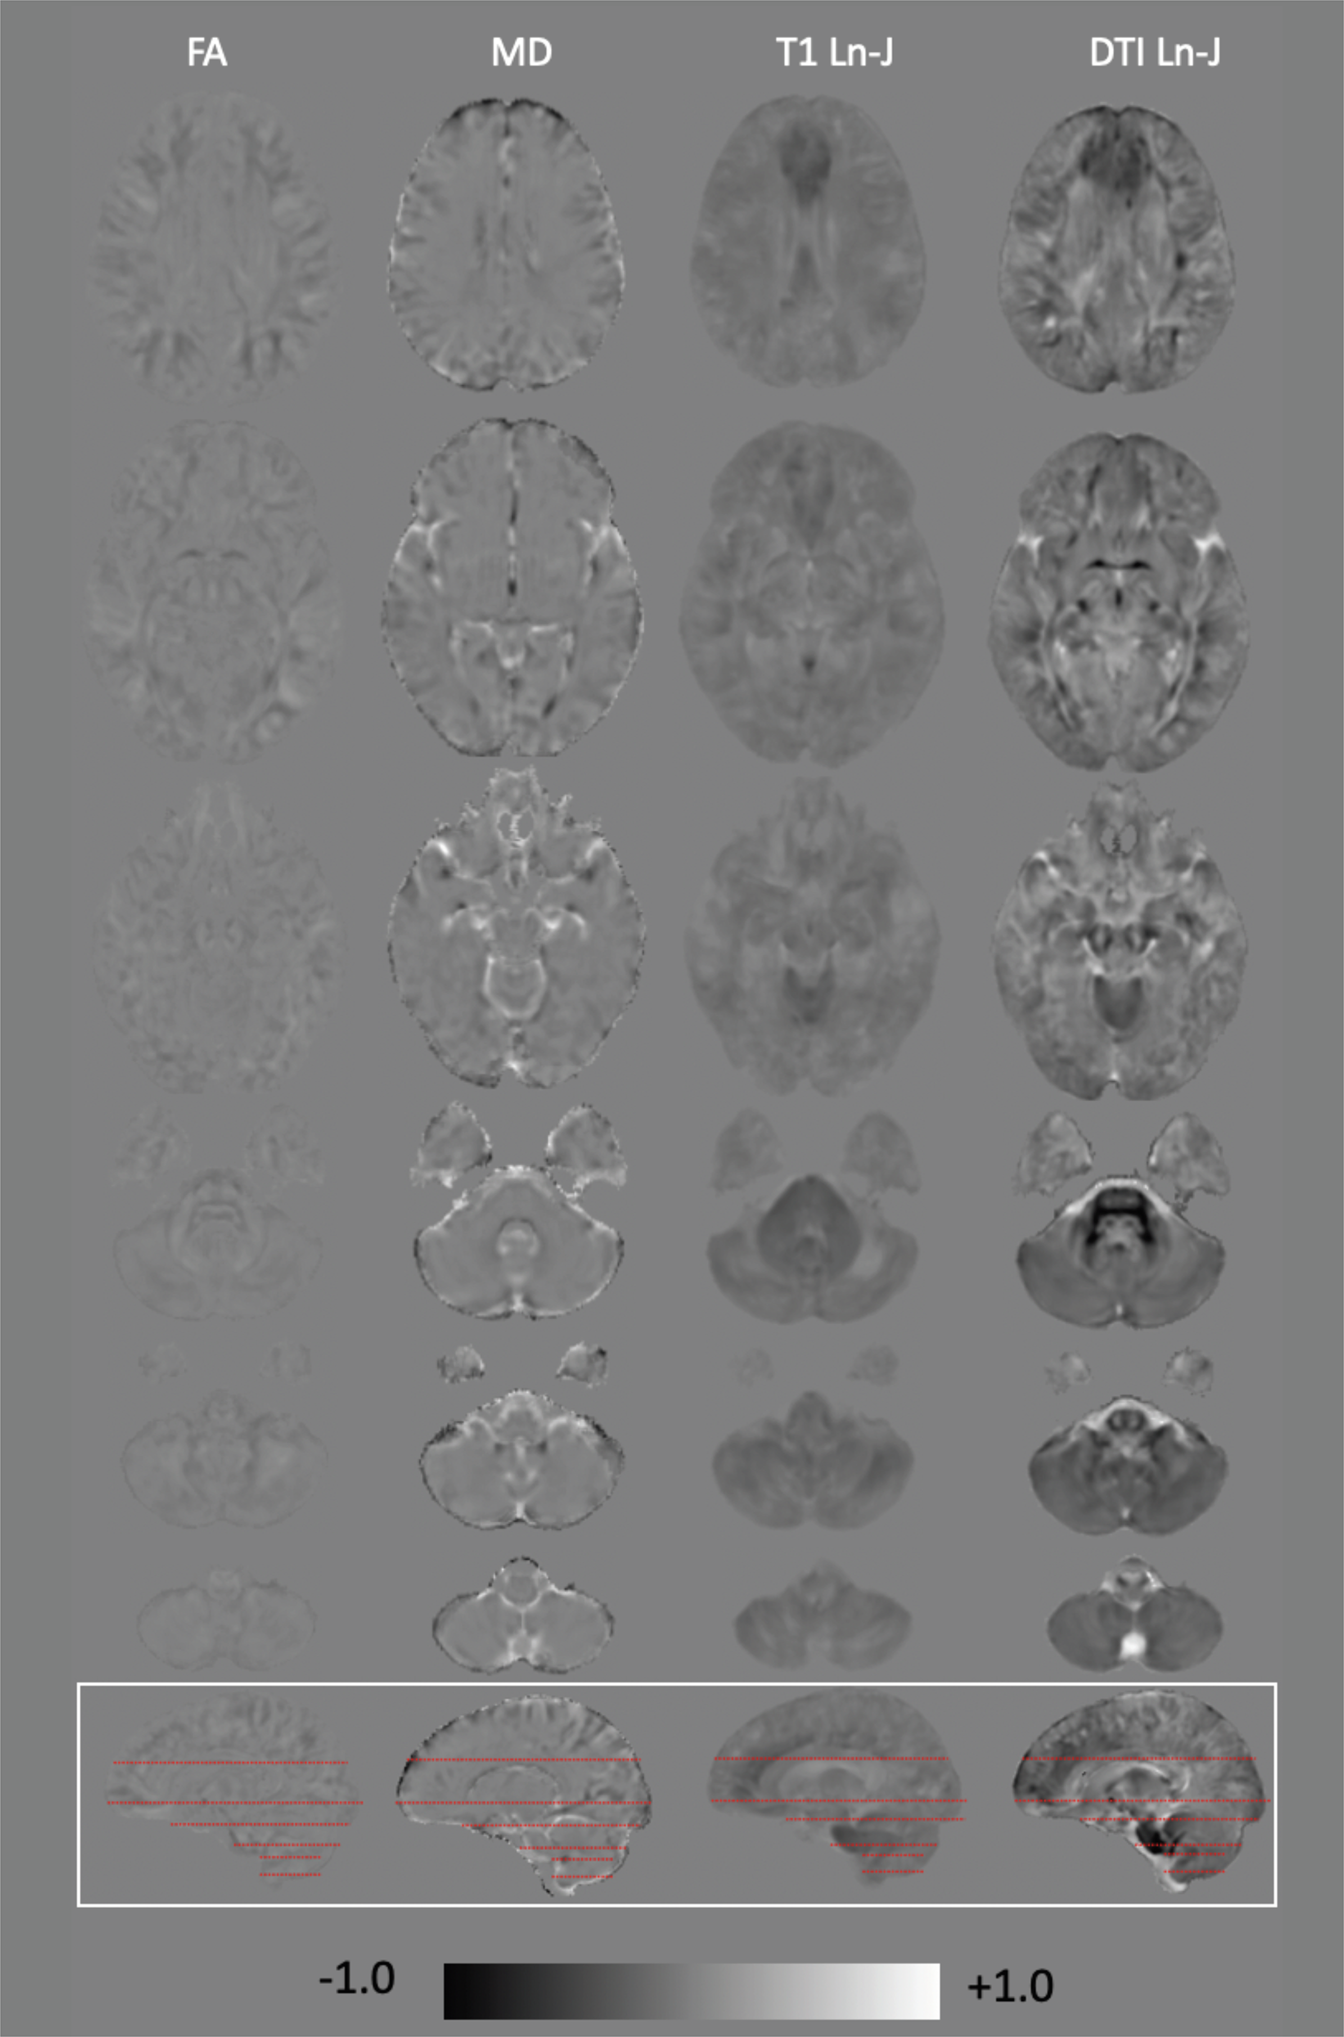

Figure 2

Magnitude difference for DS-TD group for FA, MD, T1-TBM and DTBM. The gray level in the background correspond to zero. Gray levels darker than the background indicate negative values (DS < TD) and gray levels brighter than background indicate positive values (DS > TD). All values are scaled from -1 (black) to +1 (white). Ln-J and FA values are dimensionless, MD values are in units of 10-3 mm2/s.